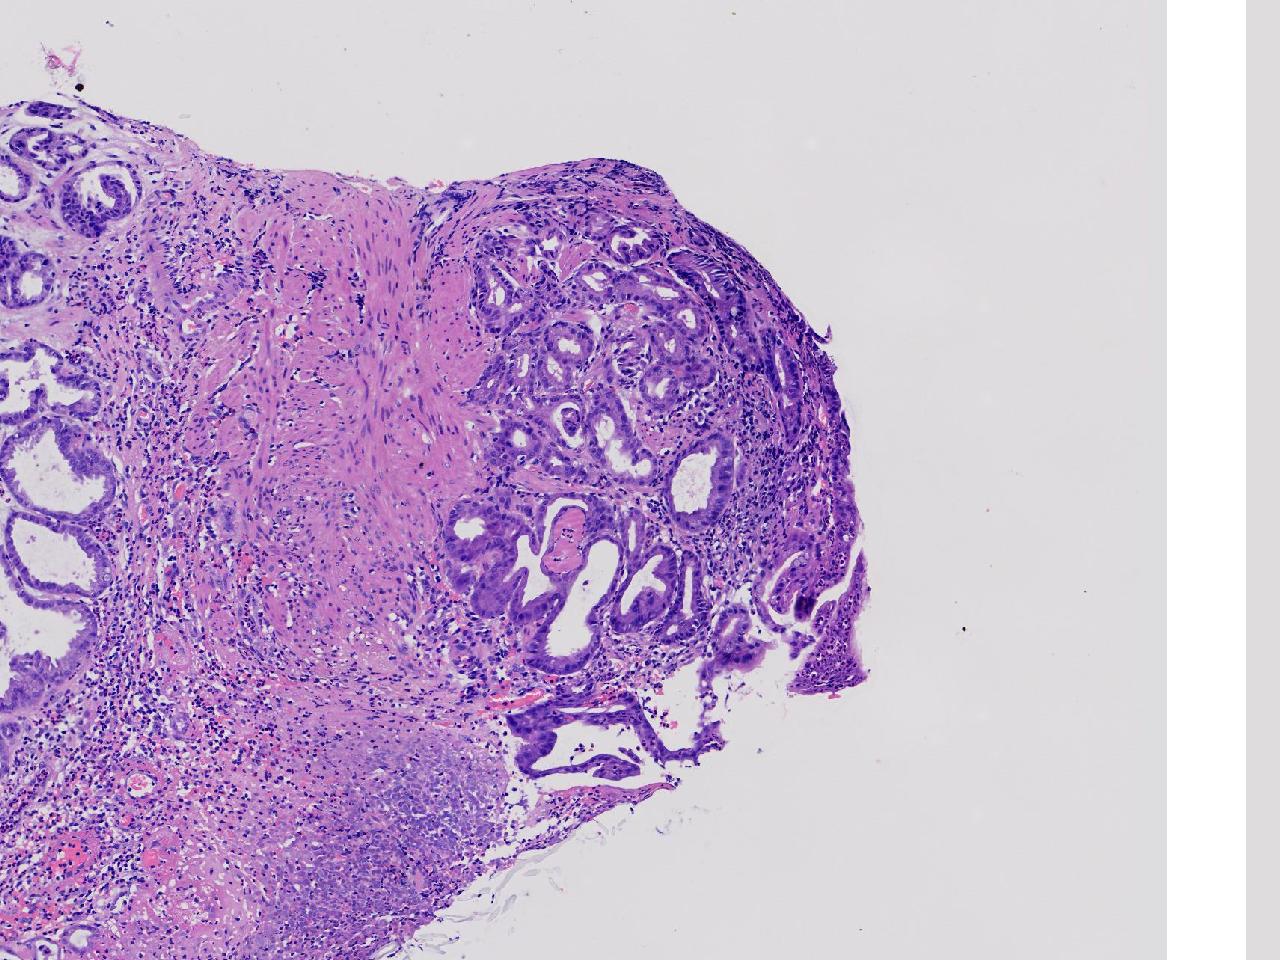

炎? 低瘤变?

胃体上部见一大小约2厘米的溃疡灶,表覆白苔,周边充血,水肿明显,活检3块。

胃体活检

灰白色不整形软组织3块,直径均0.2厘米。

深在性囊性胃炎,少量溃疡组织

深在性囊性胃炎伴溃疡